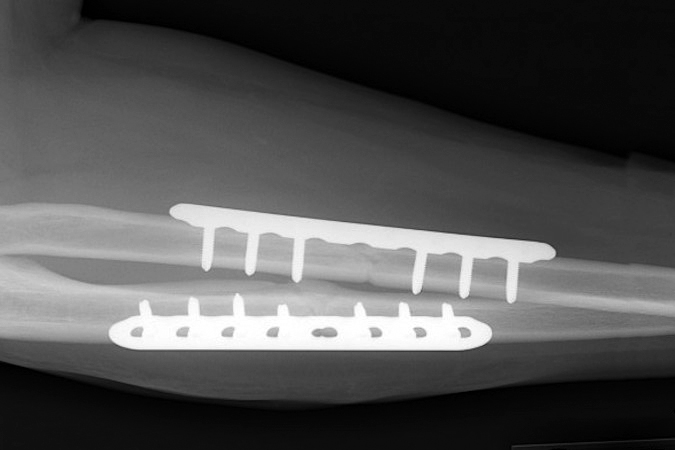

Radial and ulnar shaft fractures are relatively common injuries. Although either the radial shaft or ulnar shaft can be fractured in isolation, in most cases both bones are injured simultaneously, and these are referred to as “both bone forearm fractures.” There is a bimodal age distribution for forearm fractures, with one peak in teenage male patients and another in women over the age of 60 years. In adults, these injuries are typically due to motor vehicle accidents, athletic injuries, and falls from height, while low-energy trauma can also produce a fracture in individuals with impaired bone quality. Although conservative treatment may be indicated in certain cases, the majority of forearm fractures are managed surgically through open reduction and internal fixation (ORIF).1-4

- Surgery is required in the majority of cases and first involves rigid fixation of the radius. This is followed by intraoperative assessment of DRUJ stability.

- Volar plate fixation

- Most common surgical approach

- Fixation may be more difficult when the fracture is in the distal third of the radius, where it may only be possible to insert two screws distal to the fracture line in these cases if using a 3.5-mm straight plate.1 Modern T-plates provide better fixation in the distal fragment by allowing additional screws in the distal fragment.